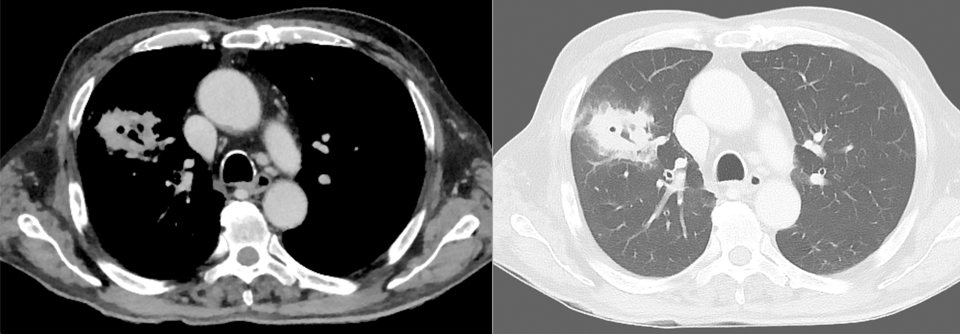

Dr. Köhler empfahl daher, alle Influenzapatienten auf Intensivstationen auf eine Aspergillose zu screenen. Dies kann im Rahmen einer Bronchoskopie mit Biopsie oder per Trachealsekret erfolgen. Zudem kann man Galactomannan im Serum oder der bronchialen Lavageflüssigkeit nachweisen.

Auch bei Coronapatienten auf Intensivstationen wurden Superinfektionen mit Aspergillus nachgewiesen. An der Uniklinik Köln war dies bei 5 von 19 Patienten mit COVID-19-assoziiertem ARDS der Fall. Vier von ihnen starben. Die Atemwegsmaterialien intensivpflichtiger Coronapatien­ten sollten unbedingt auf Pilze untersucht werden, um ggf. eine entsprechende Therapie einleiten zu können, forderte Dr. Köhler.